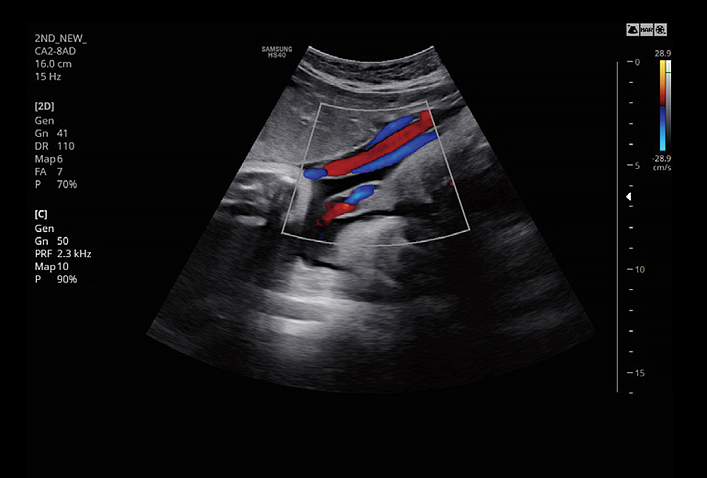

CrystalVue™ is an advanced volume rendering technology that enhances visualization of both internal and external structures in a single rendered image using a combination of intensity, gradient and position